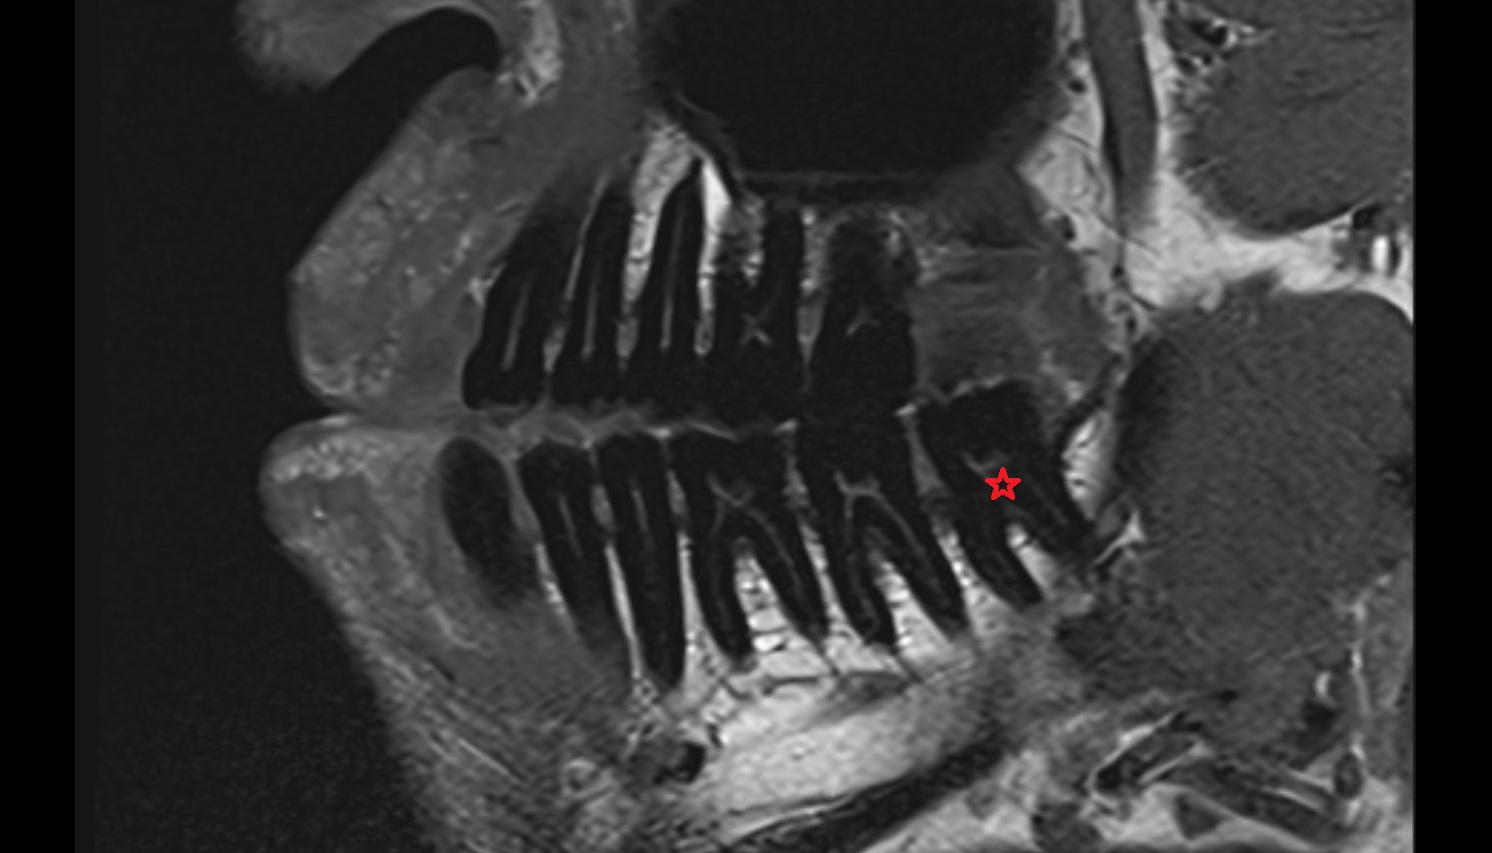

- Mandibular canal

- inferior alveolar artery

- Inferior alveolar nerve

- Mental nerve

- Root of lower molar tooth

- Lower molar apical foramen

- Upper premolar apical foramen

- Root of upper molar tooth

- Root canal of upper molar tooth

- Dental pulp of upper molar tooth

- Dental pulp of upper premolar tooth

- Enamel of lower molar tooth

- Mandibular nerve

- Dental pulp of lower molar tooth

- Root canal of lower premolar tooth

- Lower premolar apical foramen

- Dental branches of inferior alveolar artery, vein, & nerve

- Alveolar process of maxilla